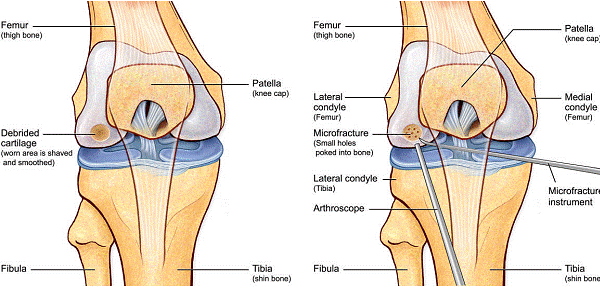

Fig.23. Diagrama microfracturi: a. Leziunea; b. Rezultatul interventiei.

Majoritatea defectelor sunt eliptice. Se masoara lungimea axei lungi si a celei scurte. Formula pentru aria elipsei este- pi x a x b/4

Aria defectului- axa lunga=a; axa scurta=b; pi=3.142

Andrelele de microfracturare cu unghi reglabil actioneaza moderat astfel incat gaurile verticale pot fi facute fara daune termice. Se fac gauri chiar de la marginea defectului.

Chirurgul trebuie sa fie foarte atent atunci cand examineaza posteriorul condililor femurali. Daca se semnaleaza orice vatamare/rana/deteriorare pe suprafetele articulare, trebuie sa se cerceteze atent calitatea cartilagiului. Orice flapsuri instabile sunt inlaturate prin folosirea unui aparat de ras electric artroscopic sau curette. Apoi, un curette este folosit pentru a debrida stratul de cartilagiu calcifiat de la baza in toata grosimea defectului. Acest pas se bazeaza pe activitatea lui Frisbi, care a demonstrat vindecarea suprafetei articulare superioare la un cal, cand stratul cartilagiului calcifiat este indepartat. Cand indepartam stratul cartilagiului calcifiat, in general nu se foloseste un aparat de ras. Cu un aparat de ras este dificil de controlat cantitatea de os eliminat, si este posibil ca osul subcondral sa fie afectat.

Dupa indepartarea cu succes a stratului de cartilaj calcifiat, o andrea este folosita pentru a face mai multe gauri mici (mirofracturi) in osul expus al defectului condral aflate la distanta de 1-2 mm. Trebuie lasata o punte de oase potrivita intre gauri. Tehnica de microfracturi are numeroase avantaje fata de foraj. Mai intai de toate, creaza o leziune termala mai mica. Mai mult, cu microfracturi, chirurgul este capabil sa intre in zonele dificile ale suprafetei articulare cu un control mai bun asupra adancimii de patrundere. La finalizarea microfracturii, o suprafata aspra este generata pentru a aderenta cheagului de sange care contine celule mezenchimale nediferentiate de la osul subcondral. Trebuie avut grija ca cele mai marginase parti ale leziuni sa fie patrunse de andrea pentru a ajuta la vindecarea tesutului reparator la imprejmuirea suprafetei articulare. Odata ce microfractura este finalizata, pompa artroscopica este oprita pentru a se asigura ca sangerarea maduvei curge din gaurile mici umpland defectul.[54]